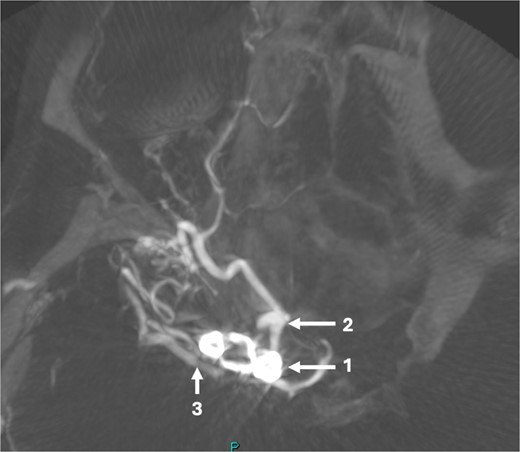

A 43-year-old lady, with known hypertension, presented with severe and sudden onset headache in 2010. Initial computed tomography (CT) head confirmed a diffuse subarachnoid haemorrhage (images not available) and a subsequent CT angiogram showed a right supraclinoid internal carotid artery (ICA) aneurysm (Fig. 1). CT Angiogram also showed an unruptured left posterior communicating which was thought not to be related to this patient’s presentation and managed conservatively with serial imaging. The patient underwent emergency craniotomy on the same day where an encircling Sundt clip was applied to secure the aneurysm. She made a full neurological recovery and was discharged from hospital. Post-operative day 1 CT angiogram demonstrated relatively normal calibre of the right A1 portion of anterior cerebral artery (ACA) and M1 portion of middle cerebral artery (MCA), in the terminal carotid region (Fig. 2).

Pre-operative CT angiogram demonstrates normal appearances of the (1) MCA, (2) ACA with, (3) laterally projecting terminal carotid sidewall aneurysm. (4) R ICA.